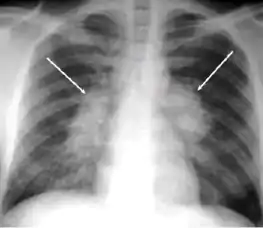

Chest X-ray of a person with advanced tuberculosis: Infection in both lungs is marked by white arrow-heads, and the formation of a cavity is marked by black arrows.